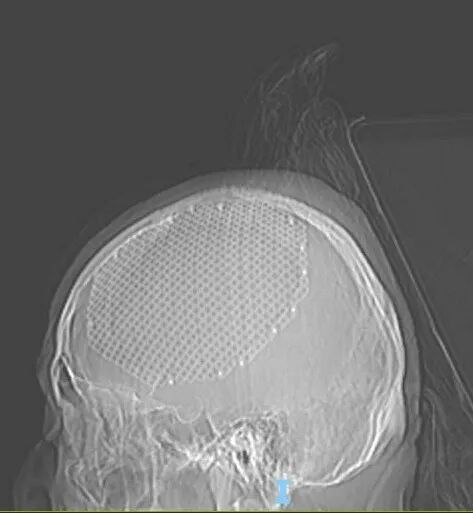

为了确保手术万无一失,王虎主任团队立即组织了严谨的术前讨论,对手术方案进行反复推敲和完善。考虑到肿瘤已侵蚀颅骨这一复杂情况,团队制定了周密的术前准备计划,决定在术中去除被侵袭的骨瓣,并采用钛网进行修补,最大限度保障患者术后的生活质量。手术当天,王虎主任带领团队沉着应战、精准操作,每一个步骤都细致入微,最终手术取得了圆满成功。

术中发现肿瘤侵蚀颅骨及硬膜